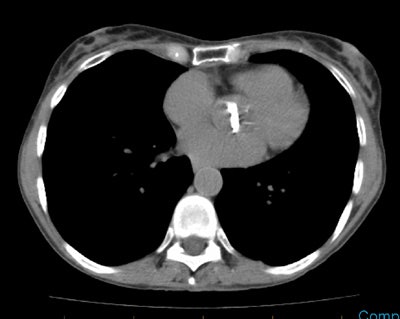

CT demonstrated a large heterogeneous mass crossing the misline which contained areas of necrosis and calcification. There is posterior rib destruction, extension into the chest wall, and a pleural effusion.